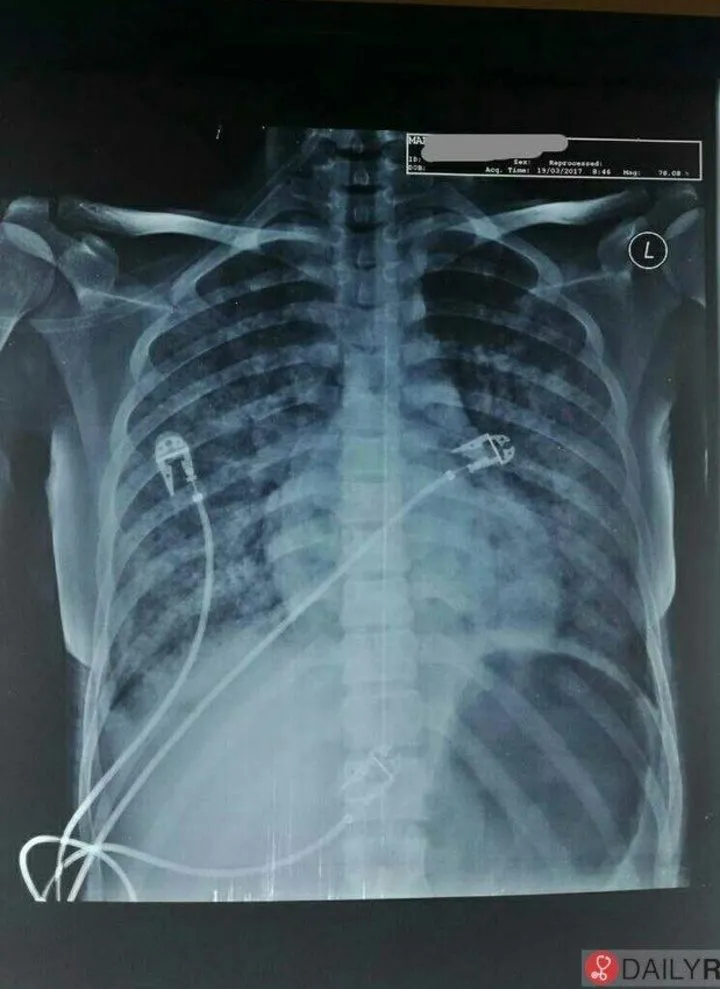

a 30 year old hiv positive male presents with fever for 3 weeks,dry cough and significant weight losss.his chest xray is given below.what is mostt likely diagnosis?

{{c1::pneumocystis jirovecii pneumonia}}

a 30 year old hiv positive male presents with fever for 3 weeks,dry cough and significant weight losss.his chest xray is given below.what is mostt likely diagnosis?<br><div><img src="c382d7db74ca0b2c59306657c38e5326.webp"></div><div>{{c1::pneumocystis jirovecii pneumonia}}<br></div>